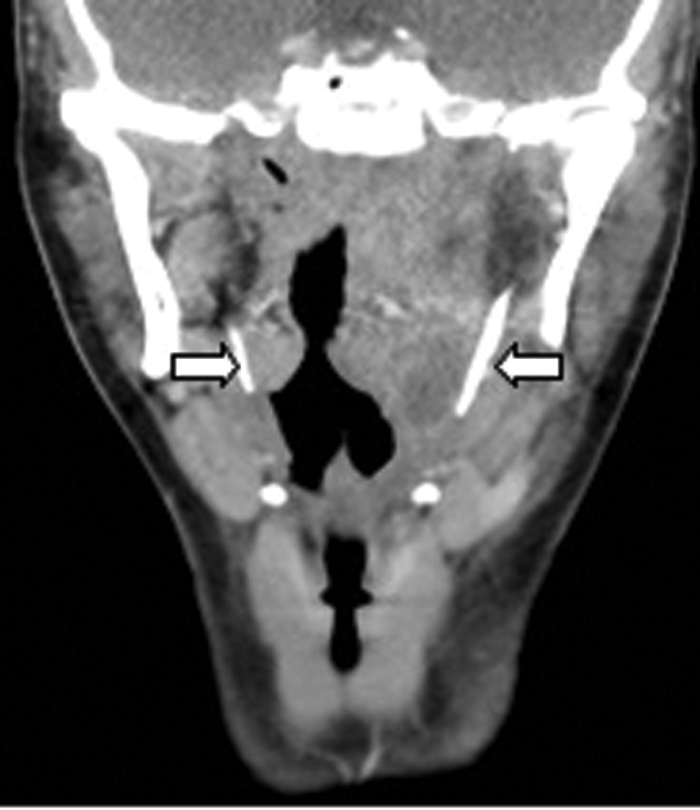

CT (Figure 8) demonstrated a left peritonsillar abscess. In addition Figure 9 shows the patient to have bilateral calcified stylohyoid ligaments. Pharyngitis / tonsillitis are common causes of referred otalgia. Additionally calcification of the stylohyoid ligament greater than 28mm can compress the glossopharyngeal nerve causing dysphagia, tinnitus and otalgia, a collection of symptoms termed as Eagle’s Syndrome.

Figure 9: Coronal contrast enhanced CT of the same patient demonstrating

bilateral calcified stylohoid ligaments (white arrows).